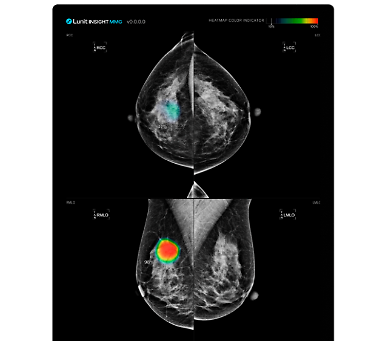

韩国医疗器械加速布局中国市场 人工智能产品备受关注据医疗器械业界24日消息,Nueyne、Corelinesoft、MEDICAL IP等韩国企业凭借先进技术,正加速布局规模高达260万亿韩元(约合人民币1.35万亿元)的中国市场。由于人工智能(AI)与数字技术融合的医疗器械在中国受到关注,韩国医疗器械企业进军势头持续升温。 近期,Nueyne通过中国当地医疗企业平台获得海南博鳌乐城国际医疗旅游先行区的快速审批,并于本月22日正式在中国推出治疗注意缺陷与多动障碍(ADHD)与发展障碍的医疗器械“Smile”。该器械采用非药物疗法,可有效提升注意力并促进认知功能发展,这一疗法避免药物治疗或